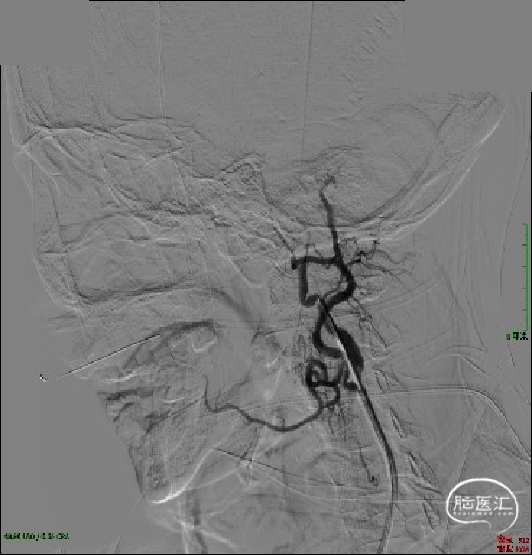

首先处理起始段狭窄-使用球囊(2×15mm、3×15mm、5×20mm)分3次逐渐扩张颈内动脉起始段。

SWIM技术取栓:半松球囊状态下Neuron Max 6F长鞘顺势送至C2段建立通路。

ACE 60再灌注导管送至血栓近端,微导丝、微导管穿过血栓至LMCA,6×30mm 取栓支架到位并释放。

双重负压抽吸下回撤取栓支架,造影见mTICI 3级再通。